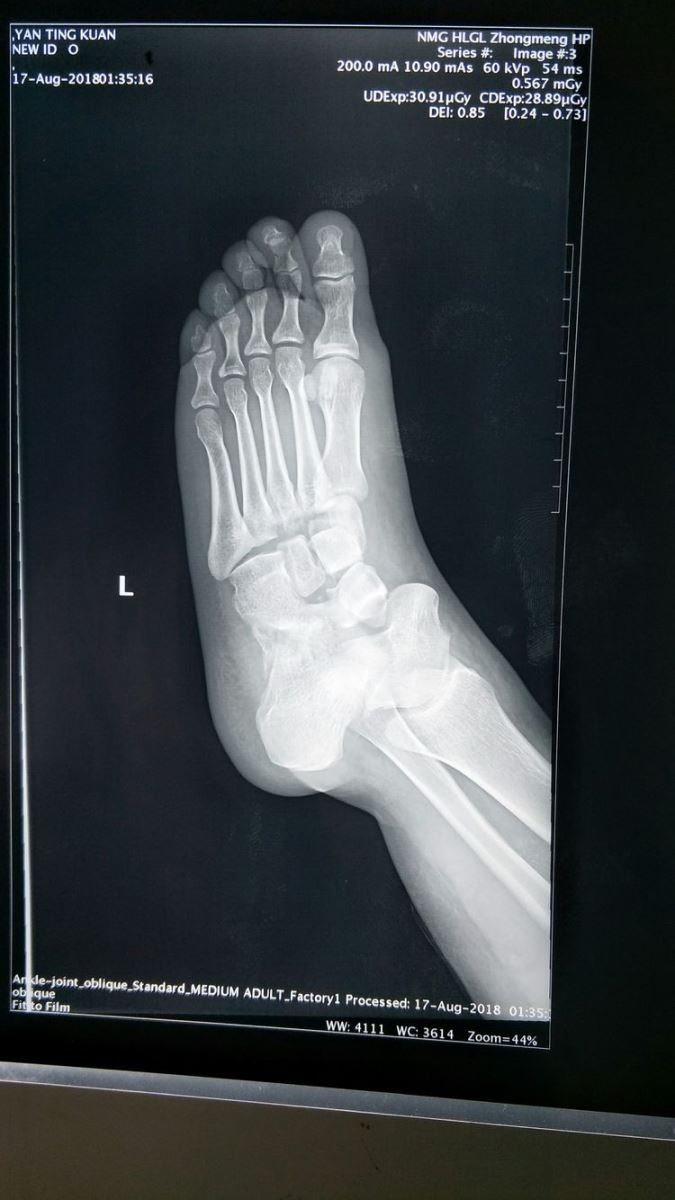

左足正位片:Chaopart关节脱位,内侧楔骨骨折,中间楔骨、外侧楔骨与骰骨之间关系紊乱,第一、二跖骨间距增宽,跖跗关节脱位。

左足斜位片:Chaopart关节脱位,跖跗关节脱位。